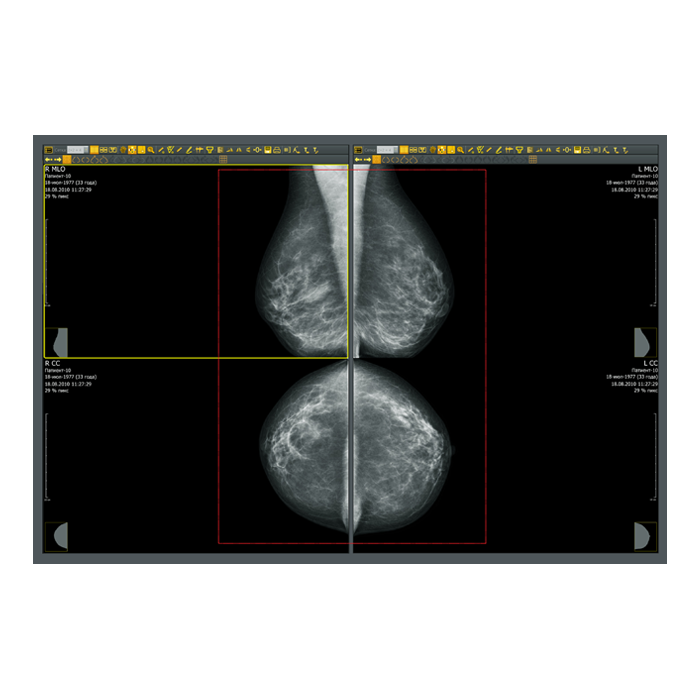

- Рентгенология